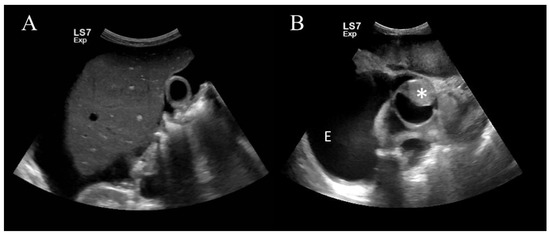

2. Case Presentation